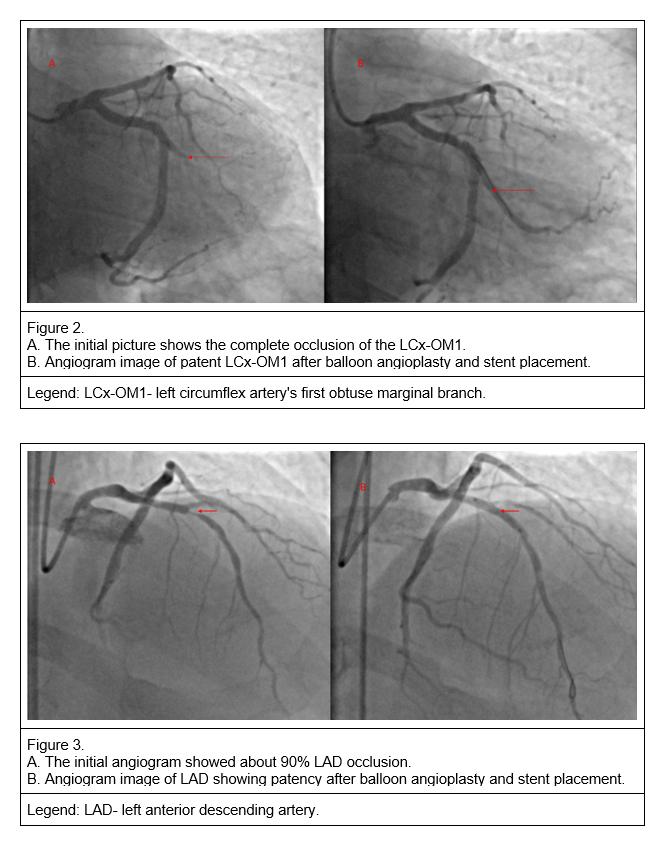

Coronary angiography shows two vessel diseases. The left circumflex artery's first obtuse marginal artery branch (LCX-OM1) received a stent in the first instance.

During the planned PTCA for treatment of LAD 48 hours after, he developed sudden bilateral loss of vision while on the table just before stent deployment.

He consented to complete the LAD PTCA the day after, which achieved the intended restenosis without complications.